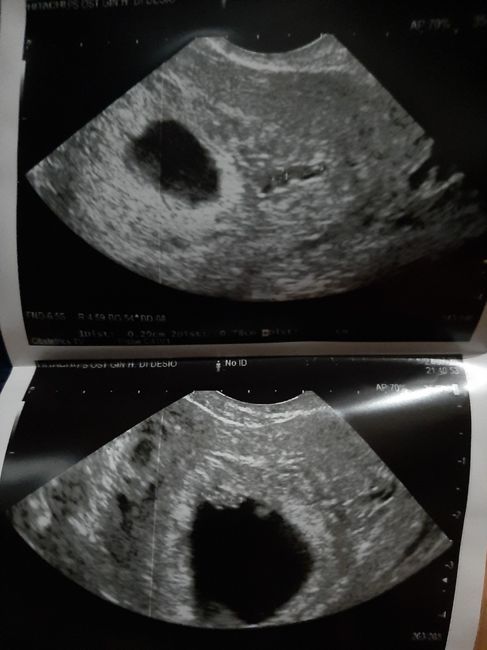

1697 giorni faCiao a tutte! Posto eco di 6+6 interna, sapete darmi il vostro parere? Grazie!